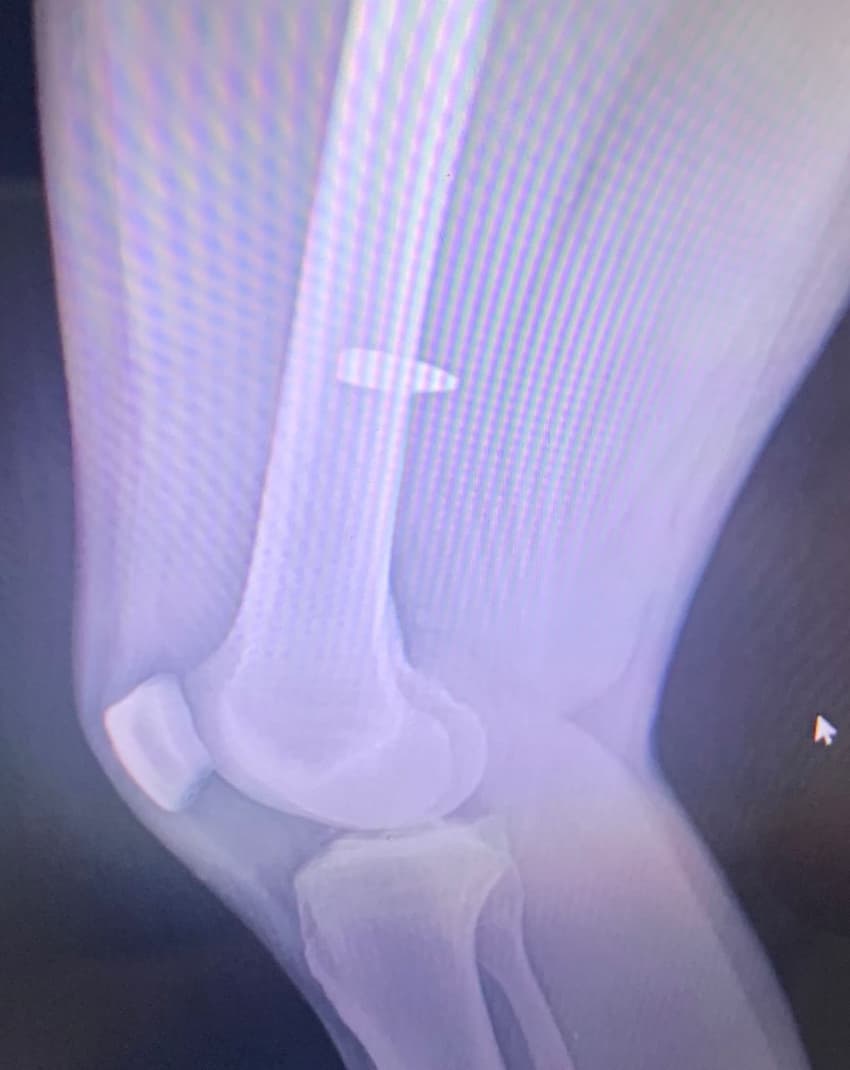

- Foi um único barulho (de tiro). A gente escutou um estalo muito próximo da gente, tipo assim, como se fosse um estalo dentro da quadra mesmo. Aí eu já senti a dor no joelho. Depois, vendo o raio X, a bala entrou bem perto do meu joelho e subiu. Então, esse barulho que a gente escutou foi ela batendo no chão e ricocheteando para cima - relatou.